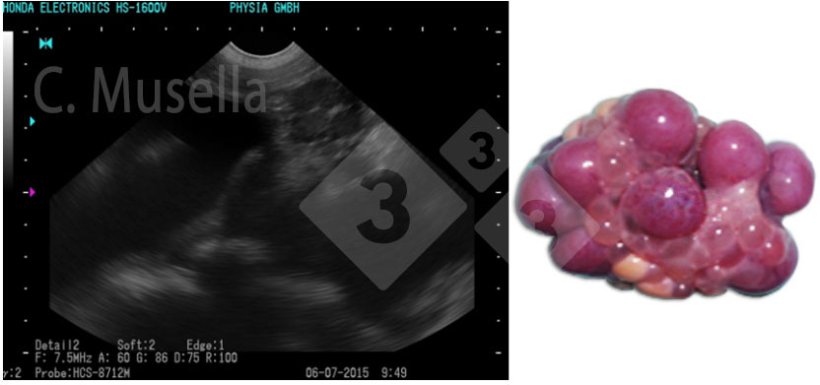

The diagnosis of single or multiple ovarian cysts is relatively simple even if the complete identification of the type of cyst through the ultrasound image is not always certain.